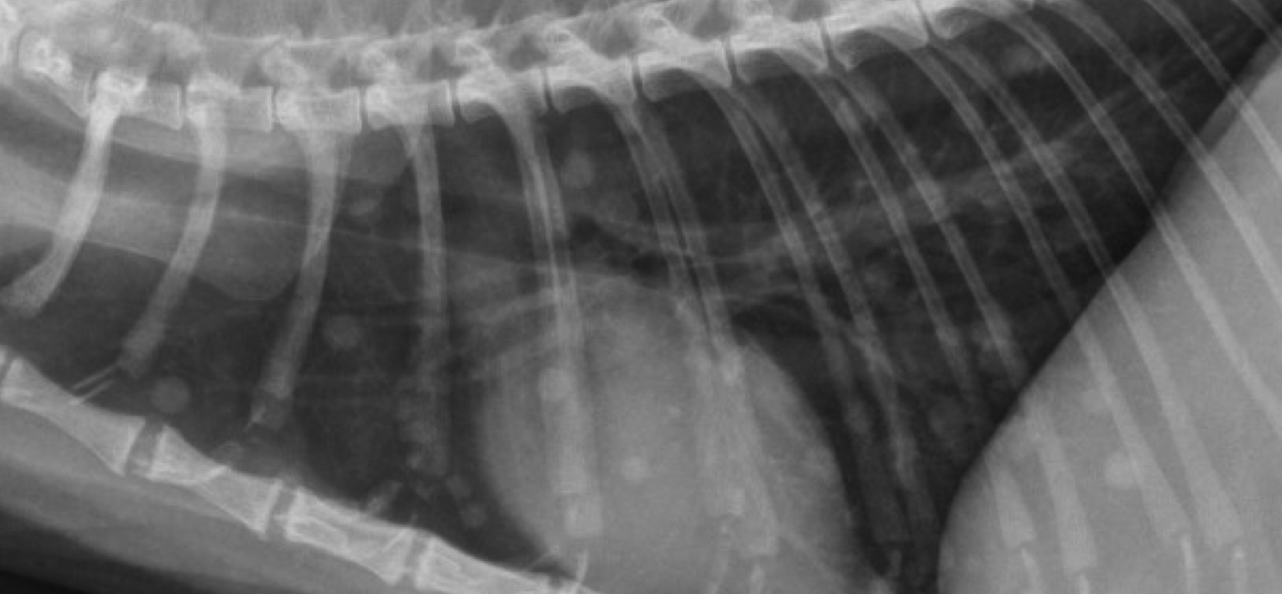

what kind of pattern

bronchial pulmonary pattern